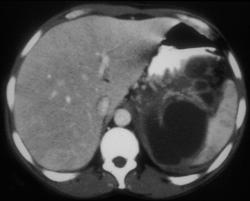

Splenic Sequestration